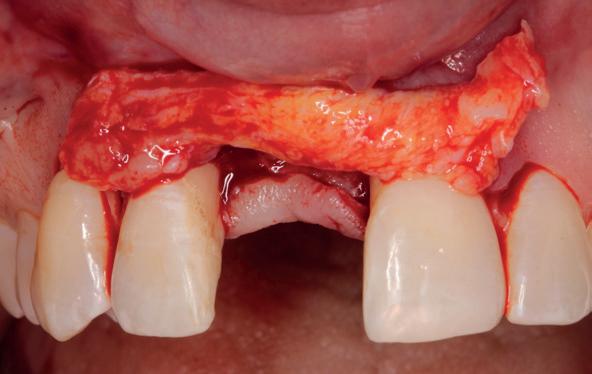

Implantologische behandelingen in het esthetische front vragen meer dan technische vaardigheid alleen. Ze vragen om overzicht, timing, vertrouwen en een team dat als vanzelf samenwerkt onder druk. Juist bij complexe casussen, waarin angst, infectie en hoge esthetische verwachtingen samenkomen, wordt zichtbaar hoe bepalend de rol van de tandartsassistent is.

Deze casus beschrijft een uitgebreide immediate implantaatbehandeling bij een patiënt die door meerdere collega’s werd geweigerd. Niet omdat de mogelijkheden ontbraken, maar omdat de complexiteit vroeg om een perfect afgestemde samenwerking. Het verhaal laat zien hoe de assistent in zo’n traject veel meer is dan een uitvoerende kracht of “mal”, maar een dynamische surgical guide die het proces mede stuurt, bewaakt en mogelijk maakt.De patiënt: wanneer alles samenkomt

Ze kwam binnen op een dinsdagochtend, iets voor achten. Een vrouw van begin zeventig, met een zachte stem en ogen die meer vertelden dan haar woorden. Ze vertelde dat ze een eigen B&B had en dat ze zich nauwelijks kon voorstellen gasten te ontvangen zonder tanden. Op dit moment kon ze echter nauwelijks lachen. “Het doet pijn… en het ruikt soms ook niet goed,” zei ze bijna verontschuldigend. Haar oude bovenbrug, die ze al meer dan twintig jaar droeg, was langzaam maar zeker ingestort. Er was sprake van cariës onder meerdere pijlers, pusafvloed,

chronische ontsteking en een brug die mobiel was en elke beet pijnlijk maakte. Ze had inmiddels meerdere tandartsen bezocht. Drie hadden haar geweigerd. Te complex. Te veel wensen. Te onvoorspelbaar.

De kern van haar vraag was eenvoudig en tegelijkertijd uitdagend: Is het mogelijk om mijn huidige brug te dupliceren en een nieuwe brug te vervaardigen met minder complicaties?

De basis van een complexe beslissing

Mijn behandelplan begint altijd met een uitgebreid klinisch onderzoek. Dat omvat een medische anamnese, intra- en extra-orale camerafoto’s en uitgebreid verwachtingsmanagement. In deze fase is mijn assistent vooral bezig met het zorgvuldig vastleggen van alle gegevens. Juist dat nauwkeurig documenteren zorgt voor rust in de behandelkamer. Minstens zo belangrijk is het luisteren naar de patiënt. Niet alleen naar de klachten, maar naar het

1. Extra-orale foto (lachlijn).

2. Beoordeling van zacht weefsel en botcontour.

3. Reflectiefoto – beoordeling van occlusievlakken en tandboog.

4. Pre-chirurgische OPG.

levensverhaal en de mens achter de brug. Begrijpen wat deze behandeling voor iemand betekent, is cruciaal voor het uiteindelijke succes.

Na het klinische onderzoek volgde het röntgenologisch traject. De CBCT liet precies zien wat we al vreesden: een front waarin het bot onregelmatig was, duidelijke radiolucenties rond de pijlers en een infectiegebied dat zich onder vrijwel de gehele brug had verspreid. Tegelijkertijd was er ook potentie. Net voldoende botstructuur om immediate implantaatplaatsing te overwegen, mits alles perfect gepland zou worden.